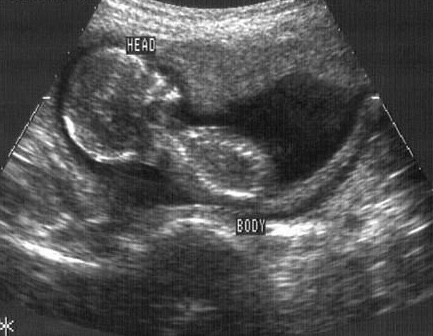

Dr Maree Lam discussed the risks and pitfalls of first trimester miscarriage and presented the significant changes which were published in the latest RANZCOG guidelines.

Recurrent miscarriage is defined as two or more miscarriages, regardless of whether they are sequential or whether there is a gestational sac. Recommendations for screening test were discussed. Recommendations for progesterone supplementation in subsequent pregnancies was discussed.